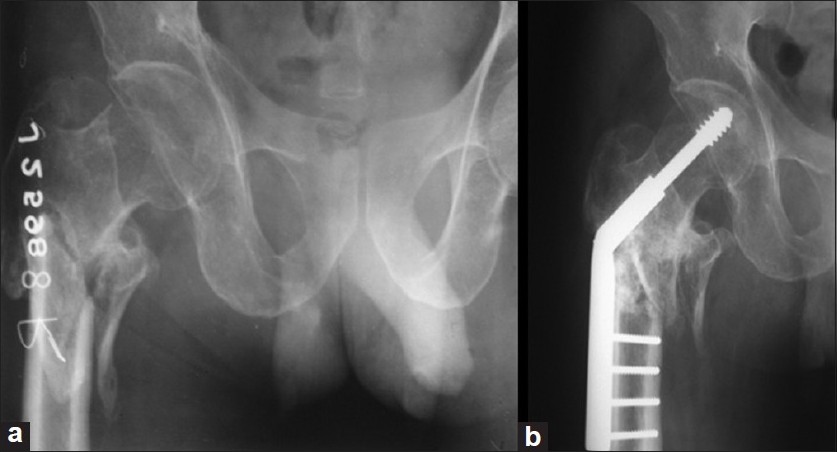

Upload Date: March 31, 2019 Full Size Image Dimensions: 837 × 452 Image Parent Post: Κατάγματα κάτω άκρου

2b.Εσωτερική οστεοσύνθεση διατροχαντήριου κατάγματος με DHS